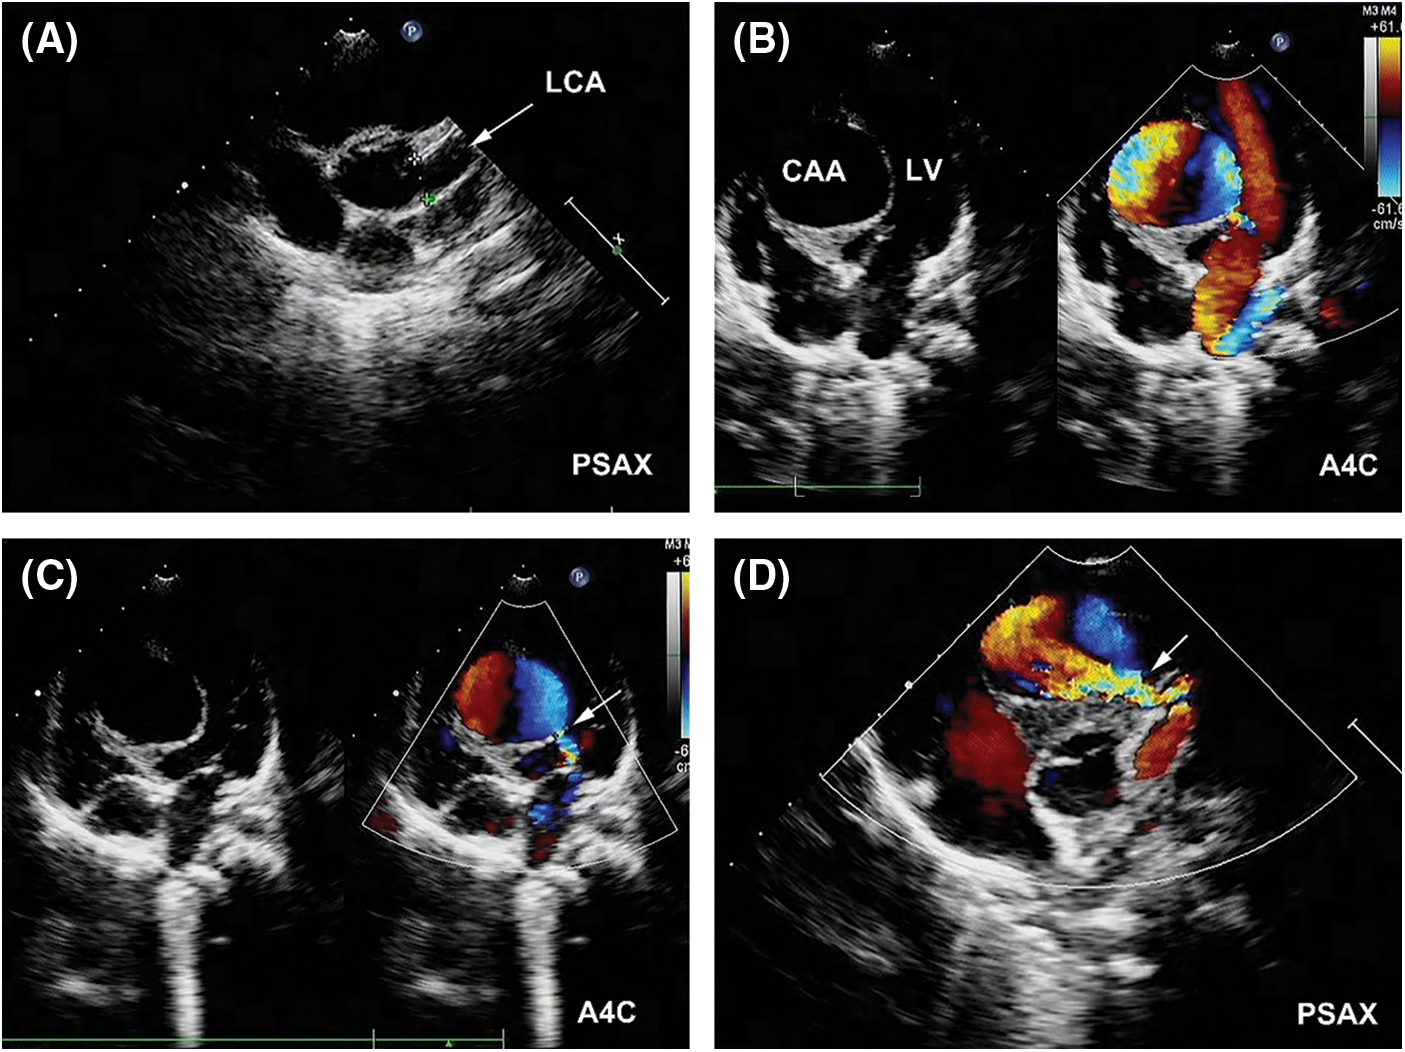

Transthoracic echocardiography (TTE) revealed a severe dilation of the LCA ostium with a giant aneurysmal coronary artery located above the intraventricular septum (IVS) (Figs. 1A and 1B). The coronary artery was draining into LV cavity through an orifice with diameter of 4.0 mm. Color Doppler flow imaging detected a continuous double-phase turbulent spectrum at the orifice, suggesting the presence of an LCA-to-LV fistula (Figs. 1C and 1D). Since no sign of left ventricular overload was present, the shunt was considered small degree. Three-dimensional computed tomography (3D-CT) scan confirmed that the fistula was proximal type, originating from anterior interventricular branch of LCA and draining into LV cavity with giant CAA of 41 mm × 28 mm in diameter (Figs. 2A and 2B). Compression of both LV and right ventricular outflow tract (RVOT) by the giant CAA was seen (Figs. 2C and 2D). If left untreated, the patient would be in danger of aneurysm rupture, thrombus formation in the CAA, and heart failure. Taking all these factors into consideration, and to relieve compression of LV and RVOT, we decided to perform transcatheter closure of both the inlet and outlet of the fistula for the patient.

Figure 1: Pre-procedual TTE revealed a LCA-to-LV fistula with giant CAA. (A) The LCA (arrow) was significantly dilated in parasternal short-axis view (PSAX). (B) A giant CAA located above the IVS with compression of LV was demonstrated in apical four-chamber view (A4C). (C) The outlet of the fistula (arrow) in LV was detected (A4C). (D) The inlet of the fistula (arrow) from LCA was detected (PSAX)